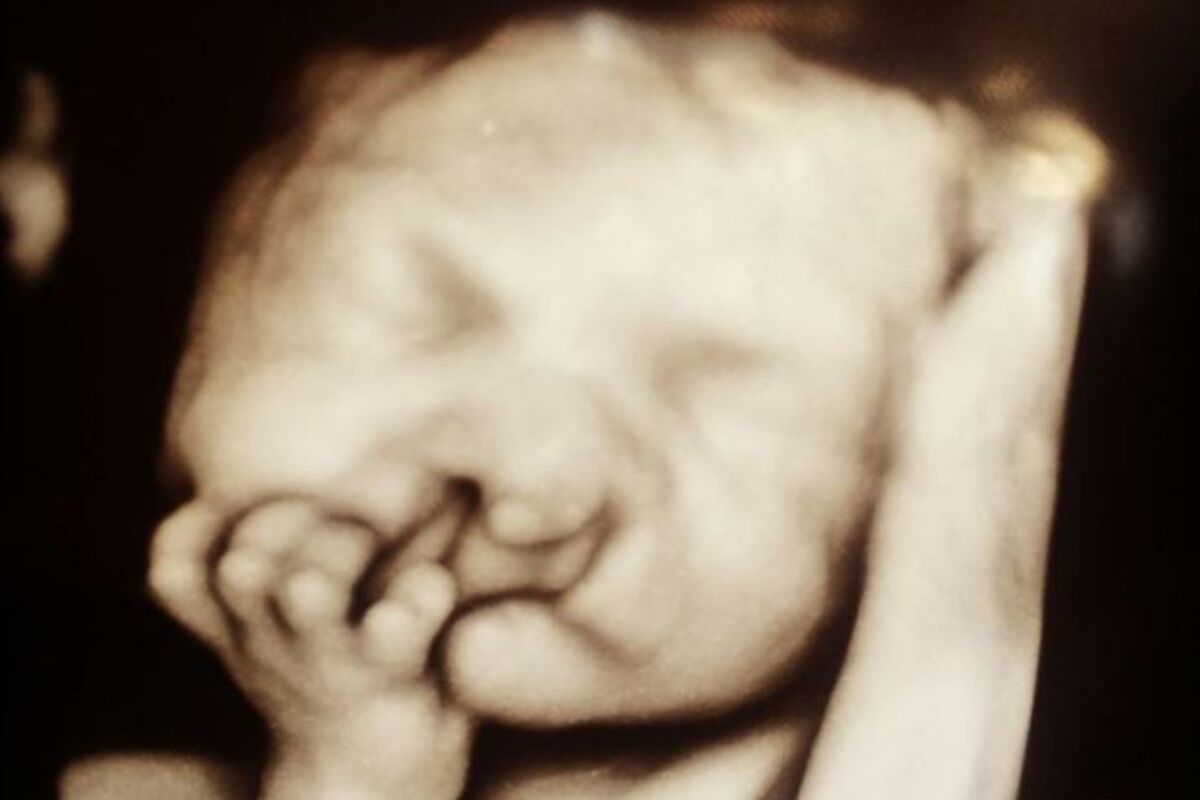

Ultrazvuk je pokazao kako će dečak biti rođen s rascepom usne i nepca zbog čega će imati i brojne druge zdravstvene probleme, pa su joj savetovali da ga pobaci.

Ipak, Sara i njen muž su odlučili da žele da svoje dete zadrže. Mali Brodi je zatim rođens retkom pojavom izbrisanog hromozoma 9 kojem nedostaje genetski kod, zbog čega će u budućnosti verojatno patiti od intelektualnih i telesnih poteškoća.